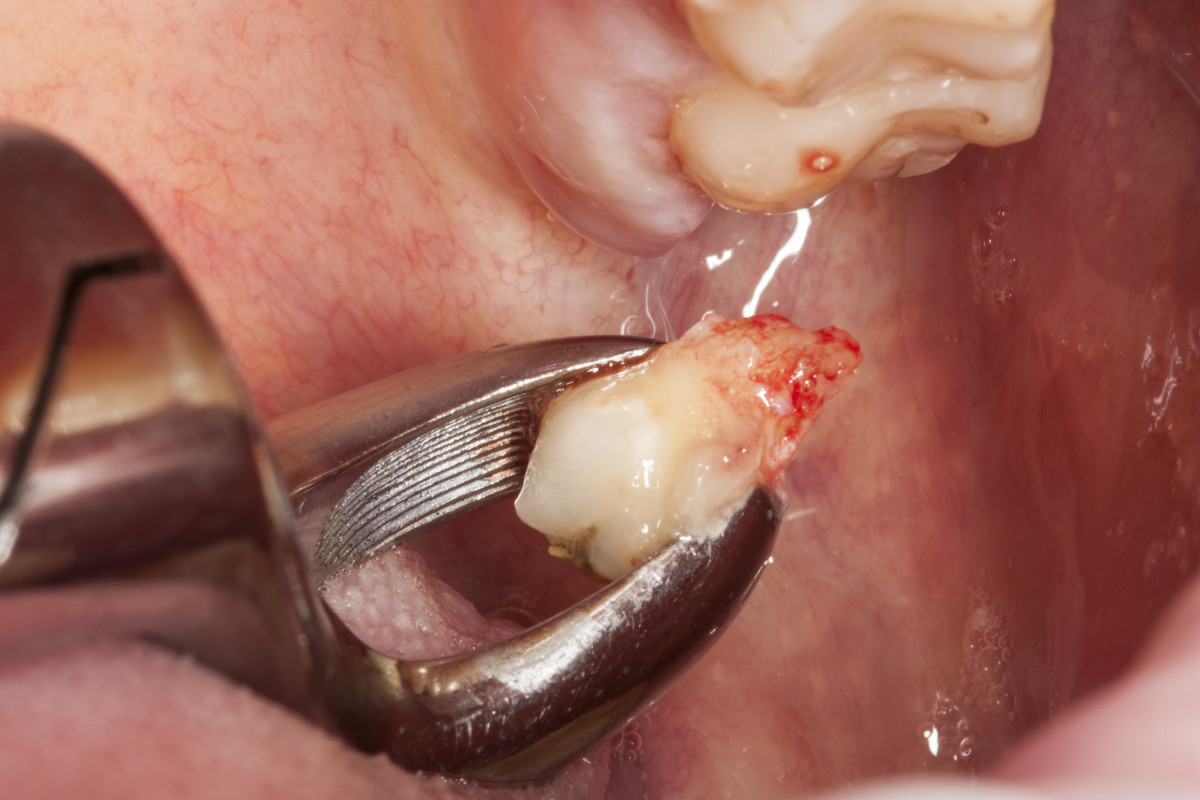

„Pacjent, który się zgłosił z dolegliwościami bólowymi górnej lewej szczęki, miał charakterystyczne objawy dla zapalenia ozębnej. Dzięki wykonaniu diagnostyki radiologicznej (zdjęcie pantomograficzne), ujawniono istnienie dziewiątego zęba, który był dodatkowo obciążony okluzyjnie. Pacjent miał otwarty zgryz – w momencie, kiedy zamykał zęby kontaktował się tylko na zębach trzonowych. To wszystko powodowało, że główny nacisk zębów był na tą malutką stożkową dziewiątkę. Przeciążenie tego zęba spowodowało to, że związanie włókien kolagenowych z podłożem kostnym osłabiło się, powstała kieszeń dziąsłowa i kieszeń kostna. To wszystko było przyczyną silnych dolegliwości bólowych o charakterze periotonditis, czyli zapaleniu wzdłuż calej długości ozębnej.

Pomimo, że ten ząb umieszczony w guzie szczęki, w miejscu bardzo odległym, niewidocznym i pacjent nie miał świadomości, że ma ząb dziewiąty, to zabieg był dość prosty, nie sprawiający kłopotów i nie wystąpiły żadne komplikacje.” –

dr Magdalena Żywicka M.Sc., kierownik medyczny placówki Stomatologia Bez Bólu